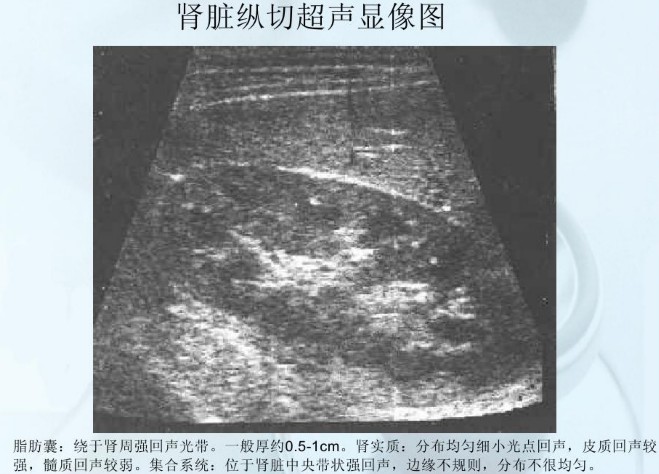

肾脏的形态像一颗蚕豆,内侧呈袋状向内凹,像一个钱包,称为肾窦(Renal sinus)。肾实质包绕肾窦,超声上显示肾实质光点亮度较低,肾窦光点亮度明显增高,位于中央呈椭圆形,内包括肾盂(Renal pelvis)、肾盏(Renal calyx)、血管等。肾盂、肾盏与输尿管(Ureter)相通。

1、肾积水:如果肾盂肾盏内含有液体时,肾窦中间出现无回声区。正常情况下,无回声区的前后径不超过1.5cm,若超过2cm时,一般诊断为肾积水。肾积水多由尿路梗阻造成,尿路梗阻的原因有结石、肿瘤、前列腺增生、输尿管狭窄等,这些都可以通过超声检查发现。

3、肾脏弥漫性病变:肾脏弥漫性病变常见于急、慢性肾小球肾炎和慢性肾病。急性肾小球肾炎在超声上主要表现为双肾体积增大,肾实质增厚;慢性肾小球肾炎晚期肾脏体积缩小,肾实质变薄,肾萎缩。

4、肾囊肿:肾囊肿的超声诊断准确率为100%。常说的肾囊肿一般是指单纯性肾囊肿,它是一种良性病变,发生率随着年龄而增长。小的肾囊肿直径仅几毫米或几厘米,壁非常薄,其内充满澄清液体,患者一般没有自觉症状;大的囊肿可形成腹部肿物。治疗方法和肝囊肿类似,预后良好。关于肾囊肿及其治疗方法、肾囊肿和多囊肾的区别、复杂性肾囊肿等,可以看看我们之前的文章:体检查出肾囊肿,我们该怎么办呢?

5、肾肿瘤:肾肿瘤以恶性占大多数,又分为肾实质肿瘤和肾盂肿瘤两类。肾实质肿瘤在超声上表现为肾局部隆起,外形异常,病变成圆形或椭圆形。肾癌早期病人往往没有明显症状,一旦出现血尿、腹痛、腹部肿块等症状时,说明肿瘤已经很大了。所以定期肾脏B超检查是早期发现肾癌最主要的手段,建议40岁后每年做一次肾脏B超检查。肾盂肿瘤的声像图特点是:在肾窦区出现占位性病变,使肾窦扩大,这类患者多伴有血尿,所以一般发现比较早。